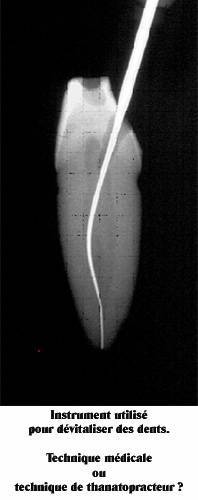

Voici le type d’instruments utilisés pour dévitaliser les dents.

Ce sont des instruments longitudinaux qui extirpent la pulpe dentaire, raclent le canal dentaire pour l’élargir et le nettoyer pour ensuite pouvoir plus facilement le remplir d’une pâte ou d’un ciment qui va durcir et obturer l’espace vidé. On comprend facilement qu’il n’est pas possible ainsi d’avoir accès aux canaux accessoires qui sont représentés sur le schéma précédent. Ceux-ci restent donc remplis de matière organique et pourrissent inéluctablement en libérant dans le sang les produits de leur putréfaction. Les dentistes grâce à cette technique ont moins l’image d’arracheurs de dents mais plutôt l’image de micro-chirurgiens conservateurs de dents. En fait dévitaliser les dents ressemble plus d’un point de vue de la technique, à une technique d’embaumement de thanatopracteur qu’à une technique médicale à proprement parler. Les instruments utilisés pour dévitaliser la dent ressemblent un peu à des poignards enfoncés dans la dent pour la tuer, et munis d’aspérités pour en sortir les entrailles. L’aspect médical réside en fait principalement dans le fait qu’on supprime ici la douleur de la dent sans l’enlever puisqu’on extirpe le nerf qui peut exprimer cette douleur. Et c’est cela qui fait que les patients sont extrêmement contents car ils n’ont plus mal et conservent leur dent d’une certaine façon grâce à l’acte de dévitalisation dentaire. Puis quand des années plus tard, ils font leur cancer ou leurs autres maladies, ils ne font jamais le lien avec cet acte de dentiste réalisé des années auparavant. Le dentiste non plus d’ailleurs, d’autant plus que la dent ne fait pas mal et qu’en apparence, elle n’a donc que des avantages. Mais en réalité, biologiquement parlant, ce n’est plus une dent mais une dent empaillée en quelque sorte et cela est très différent. Mais ce n’est pas tout. L’histologie (la science des tissus biologiques) nous enseigne que la dentine ou l’ivoire qui constitue la masse de la dent n’est pas non plus de la pierre mais ressemble plutôt à une éponge constituée de millions de minuscules canaux, les canalicules ou tubulis dentinaires qui sont eux même remplis de matière organique. Ce sont les prolongements des cellules de la pulpe, les odontoblastes, qui fabriquent l’ivoire ou dentine. Ces tubulis dans la dent dévitalisée deviennent eux aussi des niches de bactéries qui sont aussi totalement indésinfectables.